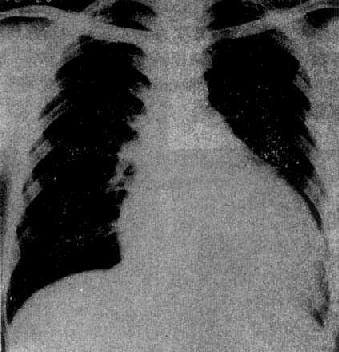

X线表现(图3-2-20),早期心大小和形状可以正常,以后心中度至高度增大,一般为双心室增大,但以左心室增大为显著,呈主动脉型;心搏动普遍减弱;肺血管纹理正常或增多,心力衰竭时,出现肺瘀血及间质性肺水肿;主动脉球一般不增大,有时因心排血量减少而缩小。继发性心肌病,病变好转后,心影恢复正常。

图3-2-20 原发性心肌病(扩张型)

心明显增大,以向左侧增大明显,

主动脉球较小,肺纹理正常